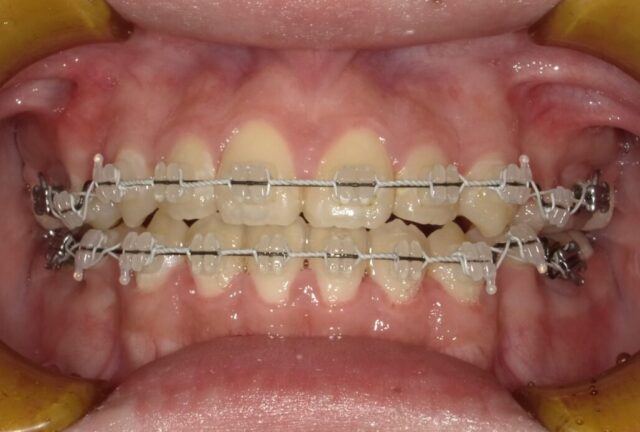

≪右側面観≫

2023年5月

2023年6月

2023年7月

2023年8月

2023年9月

2023年10月

2023年11月

2023年12月

2024年1月

2024年2月

2024年3月

2024年4月

2024年5月

2024年6月

2024年7月

2024年8月

2024年9月

2024年10月

2024年12月

2025年1月

≪左側面観≫